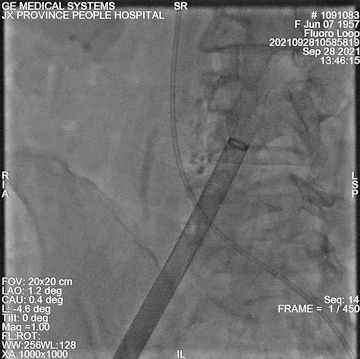

瓣膜定位

释放后

最终造影

术中情况:术中超声及造影评估,左冠灌注未受影响,瓣膜释放后无明显下滑,洪浪院长术中使用VitaFlow Liberty™进行操作,并精准释放,超声及时辅助评估,VitaFlow二代可回收功能给术者增加信心,可以更放心、大胆的挑战高风险病例。

在多学科协作下,江西省心血管病医院完成江西省首例VitaFlow Liberty™,进入电动可回收TAVR新时代!该患者主动脉瓣重度狭窄,且CT评估左冠高风险,洪浪院长TAVR团队默契配合,术前充分评估每个重要环节及其应对措施,为手术的成功奠定了基础。患者平均跨瓣压差由术前的67mmHg降至1mmHg,少量瓣周漏,手术取得圆满成功。相比传统开放手术,经股动脉的TAVR不需要体外循环,不需要开胸,没有明显失血,麻醉时间更短,创伤小、恢复快。主动脉瓣膜介入治疗从10年前的前沿探索到现在逐步成为一种主流手术模式,我国瓣膜介入技术正在发生翻天覆地的变化,在此背景下,江西省心血管病医院洪浪院长带领团队不断创新,不断提高团队技术水平,挽救患者生命和提高老年患者生活质量。